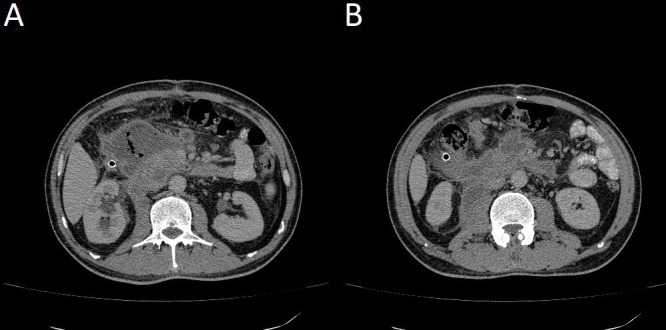

Abstract Image